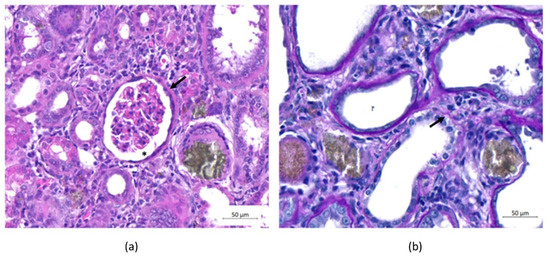

Histological observations of renal sections from all animals with CKD revealed thickening of the Bowman’s capsule, hypertrophy of the capsular space and discontinuity of the basal lamina (Figure 5).

Figure 5.

Histopathological evaluation of the kidneys. (a) Hematoxylin and eosin (H&E) staining and (b) Schiff’s periodic acid (PAS) staining. (a) The animals were evaluated on Day 30, and an increase in Bowman’s capsule thickness (arrow) and capsular space hypertrophy (asterisk) was observed in all groups. (b) Discontinuity of the basal blade (arrow) was observed in all groups. Scale bar: 50 µm.